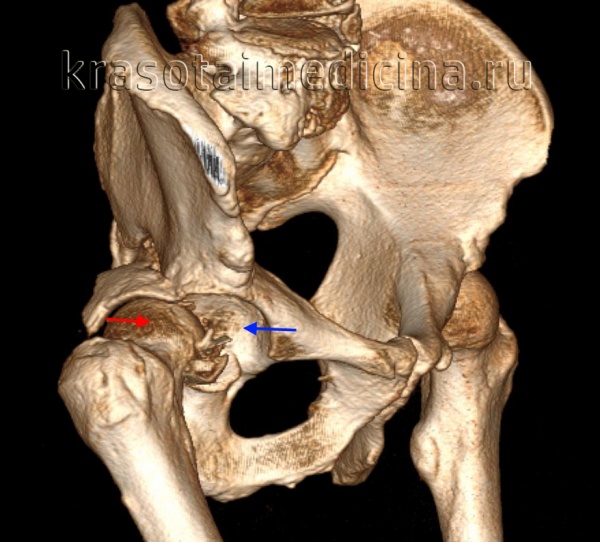

Диагностика вывихов бедра, как правило, не вызывает затруднений у врача-травматолога. Для уточнения положения головки бедренной кости и исключения возможных костных повреждений проводится рентгенологическое исследование в двух проекциях или МРТ тазобедренного сустава.

КТ таза. 3D-реконструкция. Красная стрелка – вывихнутая головка бедренной кости, синяя стрелка – «пустая» вертлужная впадина.